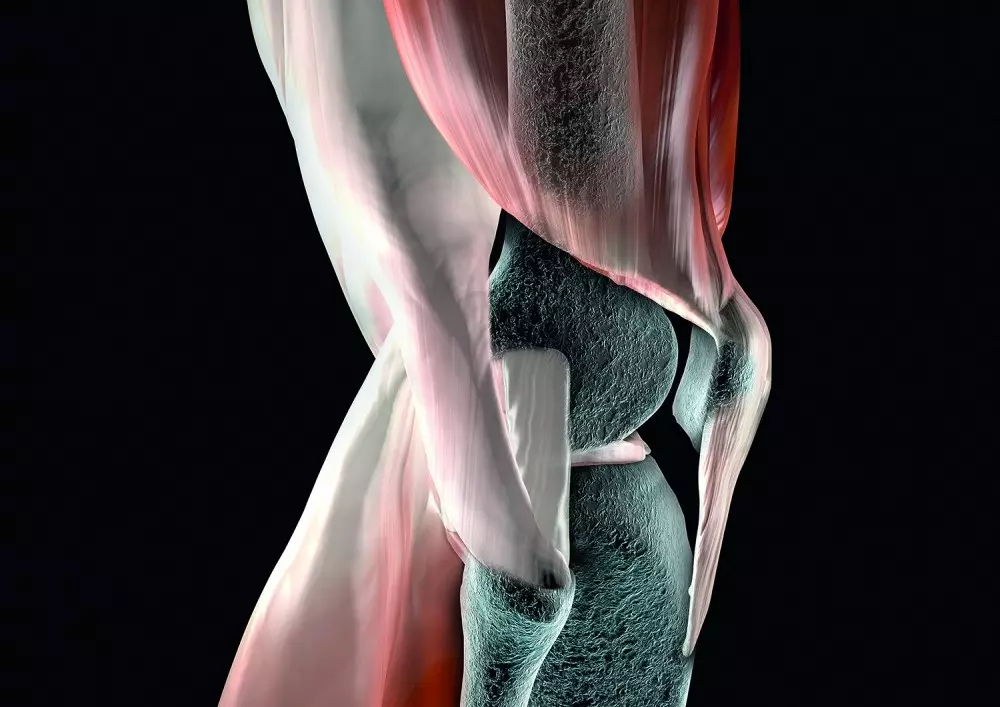

Metoda McKenziego w rwie kulszowej

W dziale „Z praktyki gabinetu” znajdą Państwo tekst pt. „Metoda McKenziego w rwie kulszowej. Opis przypadku”. Bóle kręgosłupa dotyczą bardzo dużej części społeczeństwa, co może mieć źródło w siedzącym trybie życia i ograniczeniu aktywności ruchowej. Choć lekarze i fizjoterapeuci nieustannie poszukują nowych metod walki z bólem, do najpopularniejszych wciąż należy właśnie metoda McKenziego. Krzysztof Czupryniak przedstawia przypadek 32-letniej kobiety, spędzającej większość czasu w pozycji siedzącej, jednak uprawiającej przy tym jogging 3 razy w tygodniu. Opisuje badanie przedmiotowe oraz poszczególne sesje fizjoterapii z wykorzystaniem wspomnianej metody.